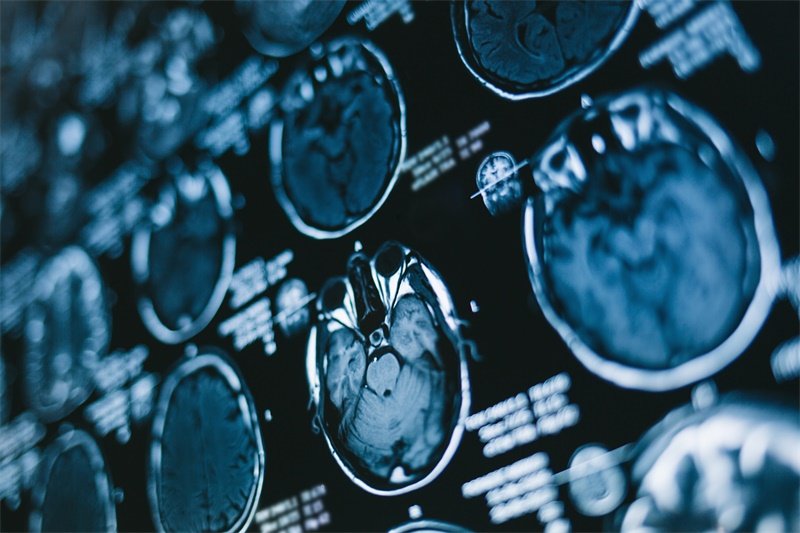

影像学检查

影像学检查是检测左侧蝶骨嵴内侧占位的主要手段。一般来说,医生会首先安排CT扫描或MRI扫描。CT扫描能够快速识别占位的存在,而MRI则在显示软组织结构方面更为清晰,能够提供更为详细的信息。